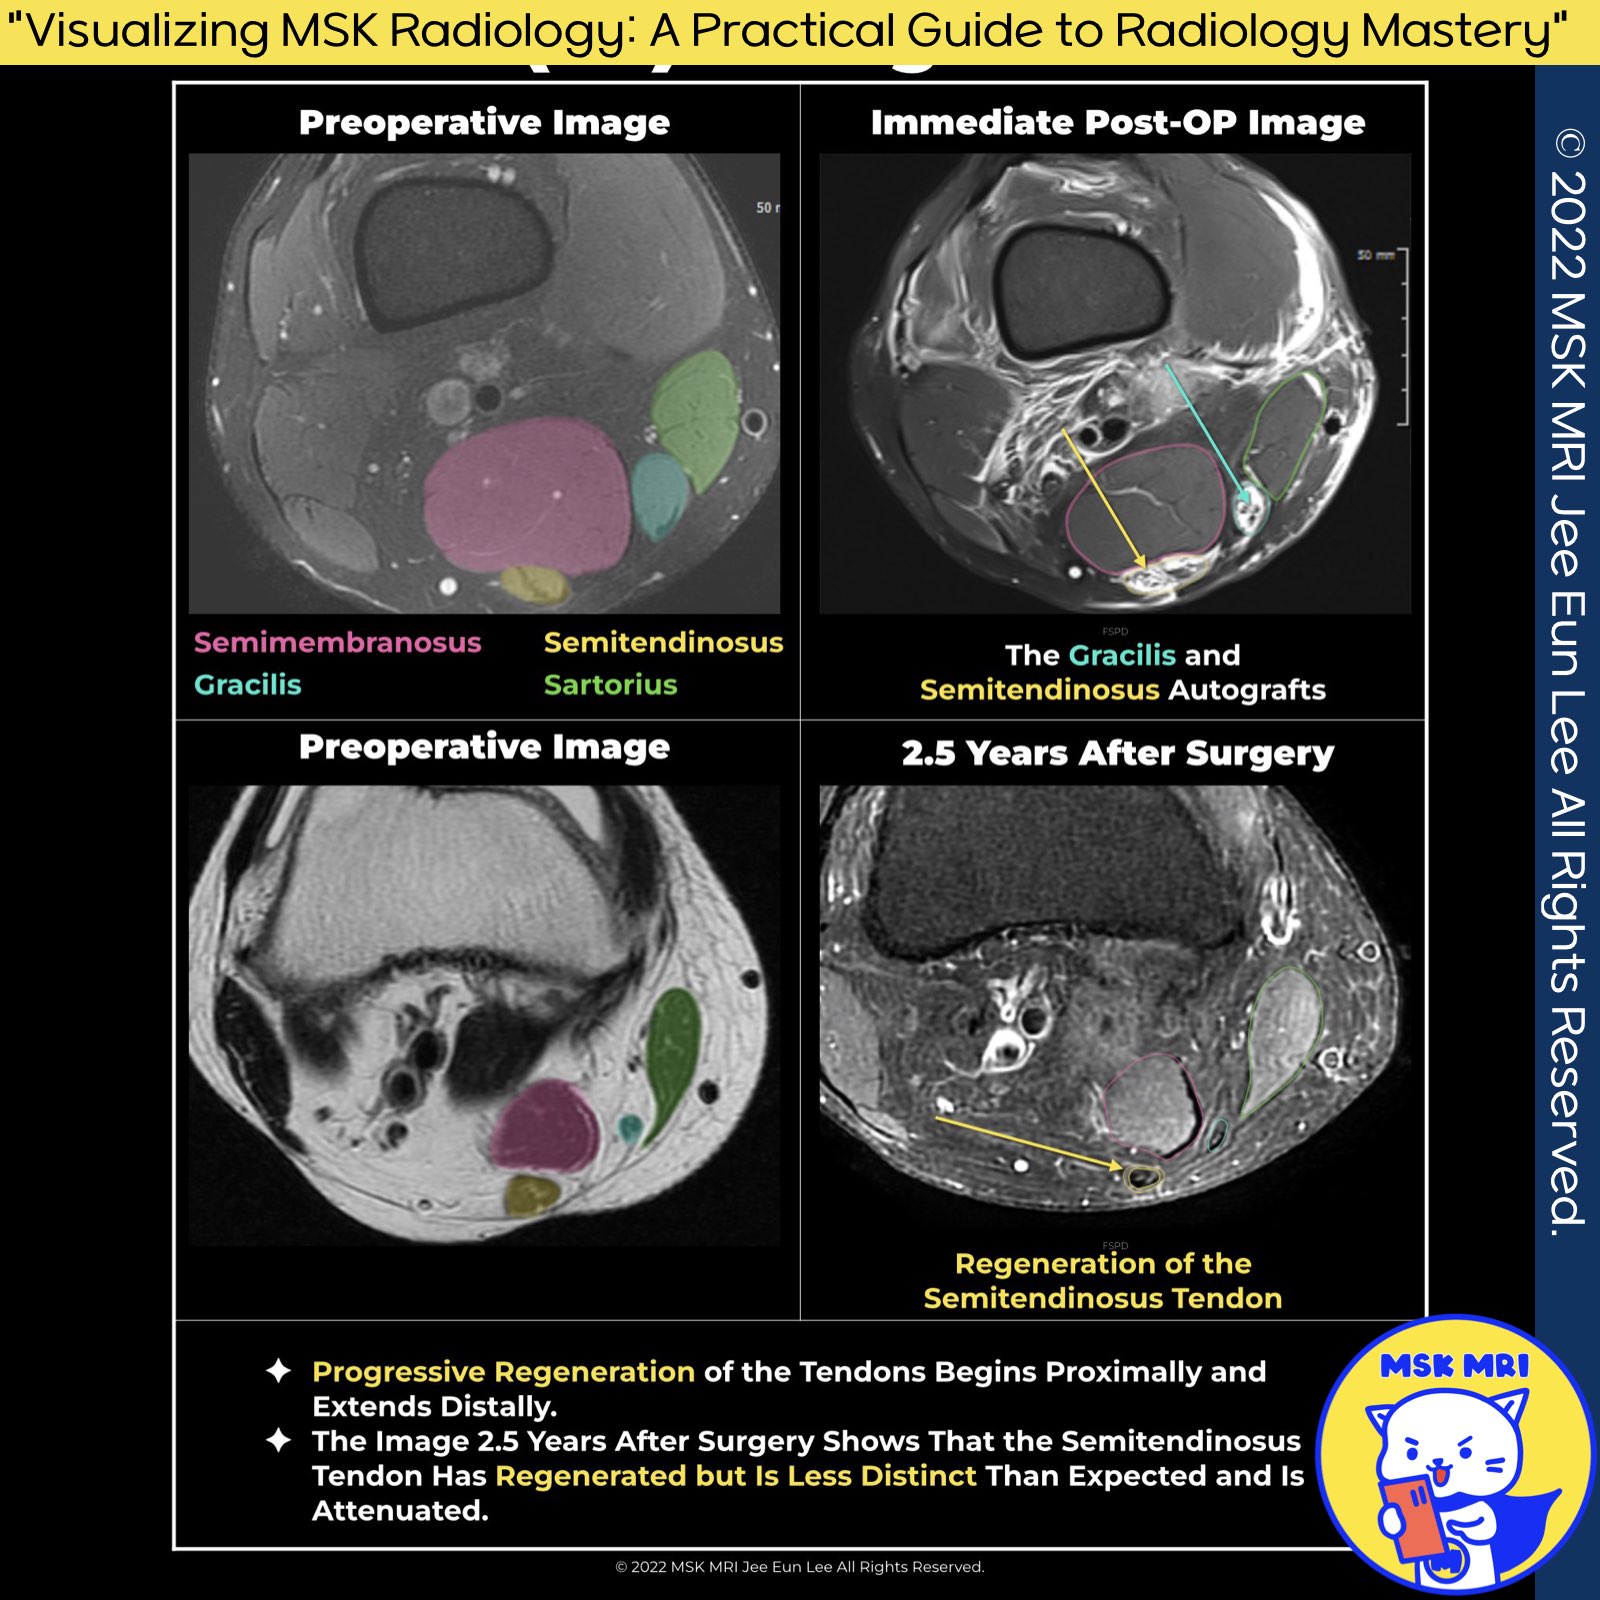

Hamstring Tendon (HT) Grafts

- The distal semitendinosus and gracilis tendons are common choices for HT autografts.

Hamstring Tendon Regeneration Overview

- Hamstring tendons show a 70% or higher regeneration rate after ACL reconstruction.

- Regeneration typically occurs within 1 month to 1 year post-harvest.

- Complete "pes anserinus" regeneration is rare, noted in only 10% of cases.

- Absence of both tendons occurs in 15% of cases.

- Initial hypertrophy followed by volume reduction, muscular atrophy, retraction, and fatty infiltration are common within the first 2 years.